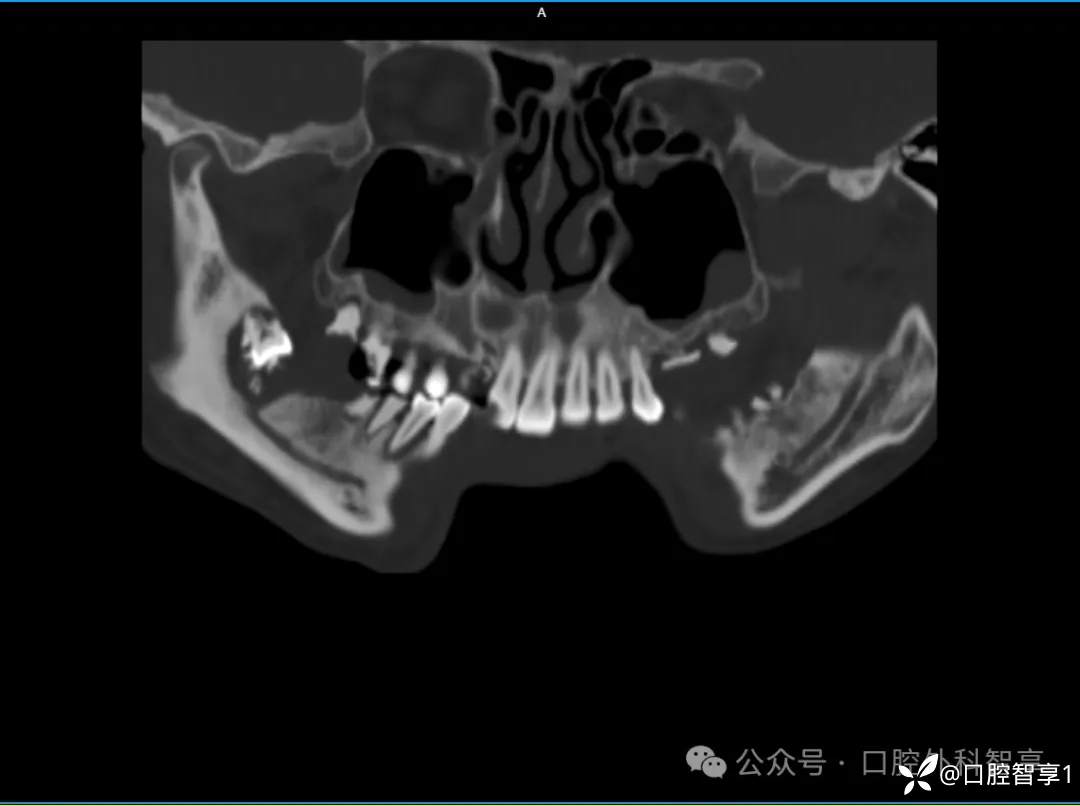

下颌骨CT示:右下颌角密度不均匀,病变部位累及下牙槽神经管,内可见下颌第三磨牙。

【临床诊断】:颌骨骨髓炎、阻生牙